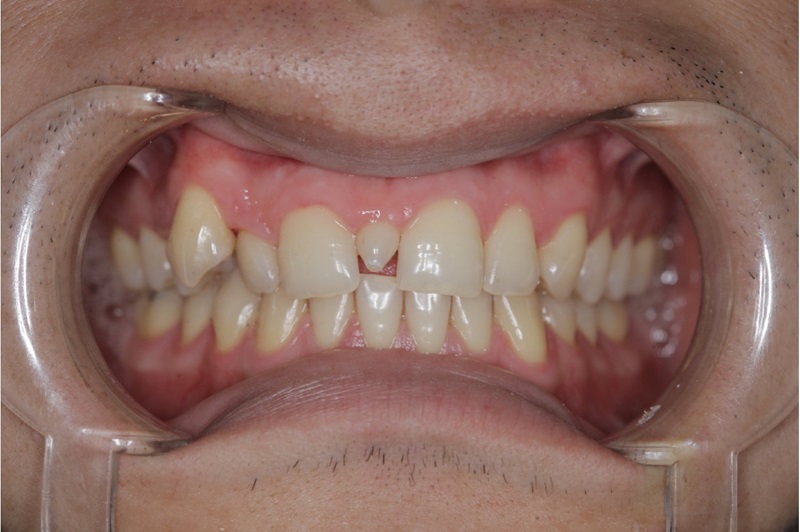

- Răng dư kẽ giữa: Là răng mọc chen vào đường giữa 2 răng cửa hàm trên.

- Răng mọc không đúng vị trí: Đây là dấu hiệu dễ thấy nhất. Bạn có thể thấy một chiếc răng mọc chen vào giữa hai răng cửa (gọi là Mesiodens), mọc lệch hẳn ra ngoài hoặc vào trong cung hàm (răng khểnh, răng mọc lẫy).

- Hình dạng răng bất thường: Răng thừa thường có kích thước nhỏ hơn, dị dạng, có hình nón hoặc hình củ, không giống hình dạng của răng bình thường.

- Răng mọc chen chúc, xô lệch: Sự xuất hiện của răng thừa chiếm mất không gian, khiến các răng vĩnh viễn khác không đủ chỗ, dẫn đến mọc chen chúc, xoay trục.

- Khe thưa lớn bất thường: Đôi khi, một răng thừa mọc ngầm giữa hai răng cửa có thể đẩy chân răng của chúng ra xa nhau, tạo ra một khe thưa lớn.